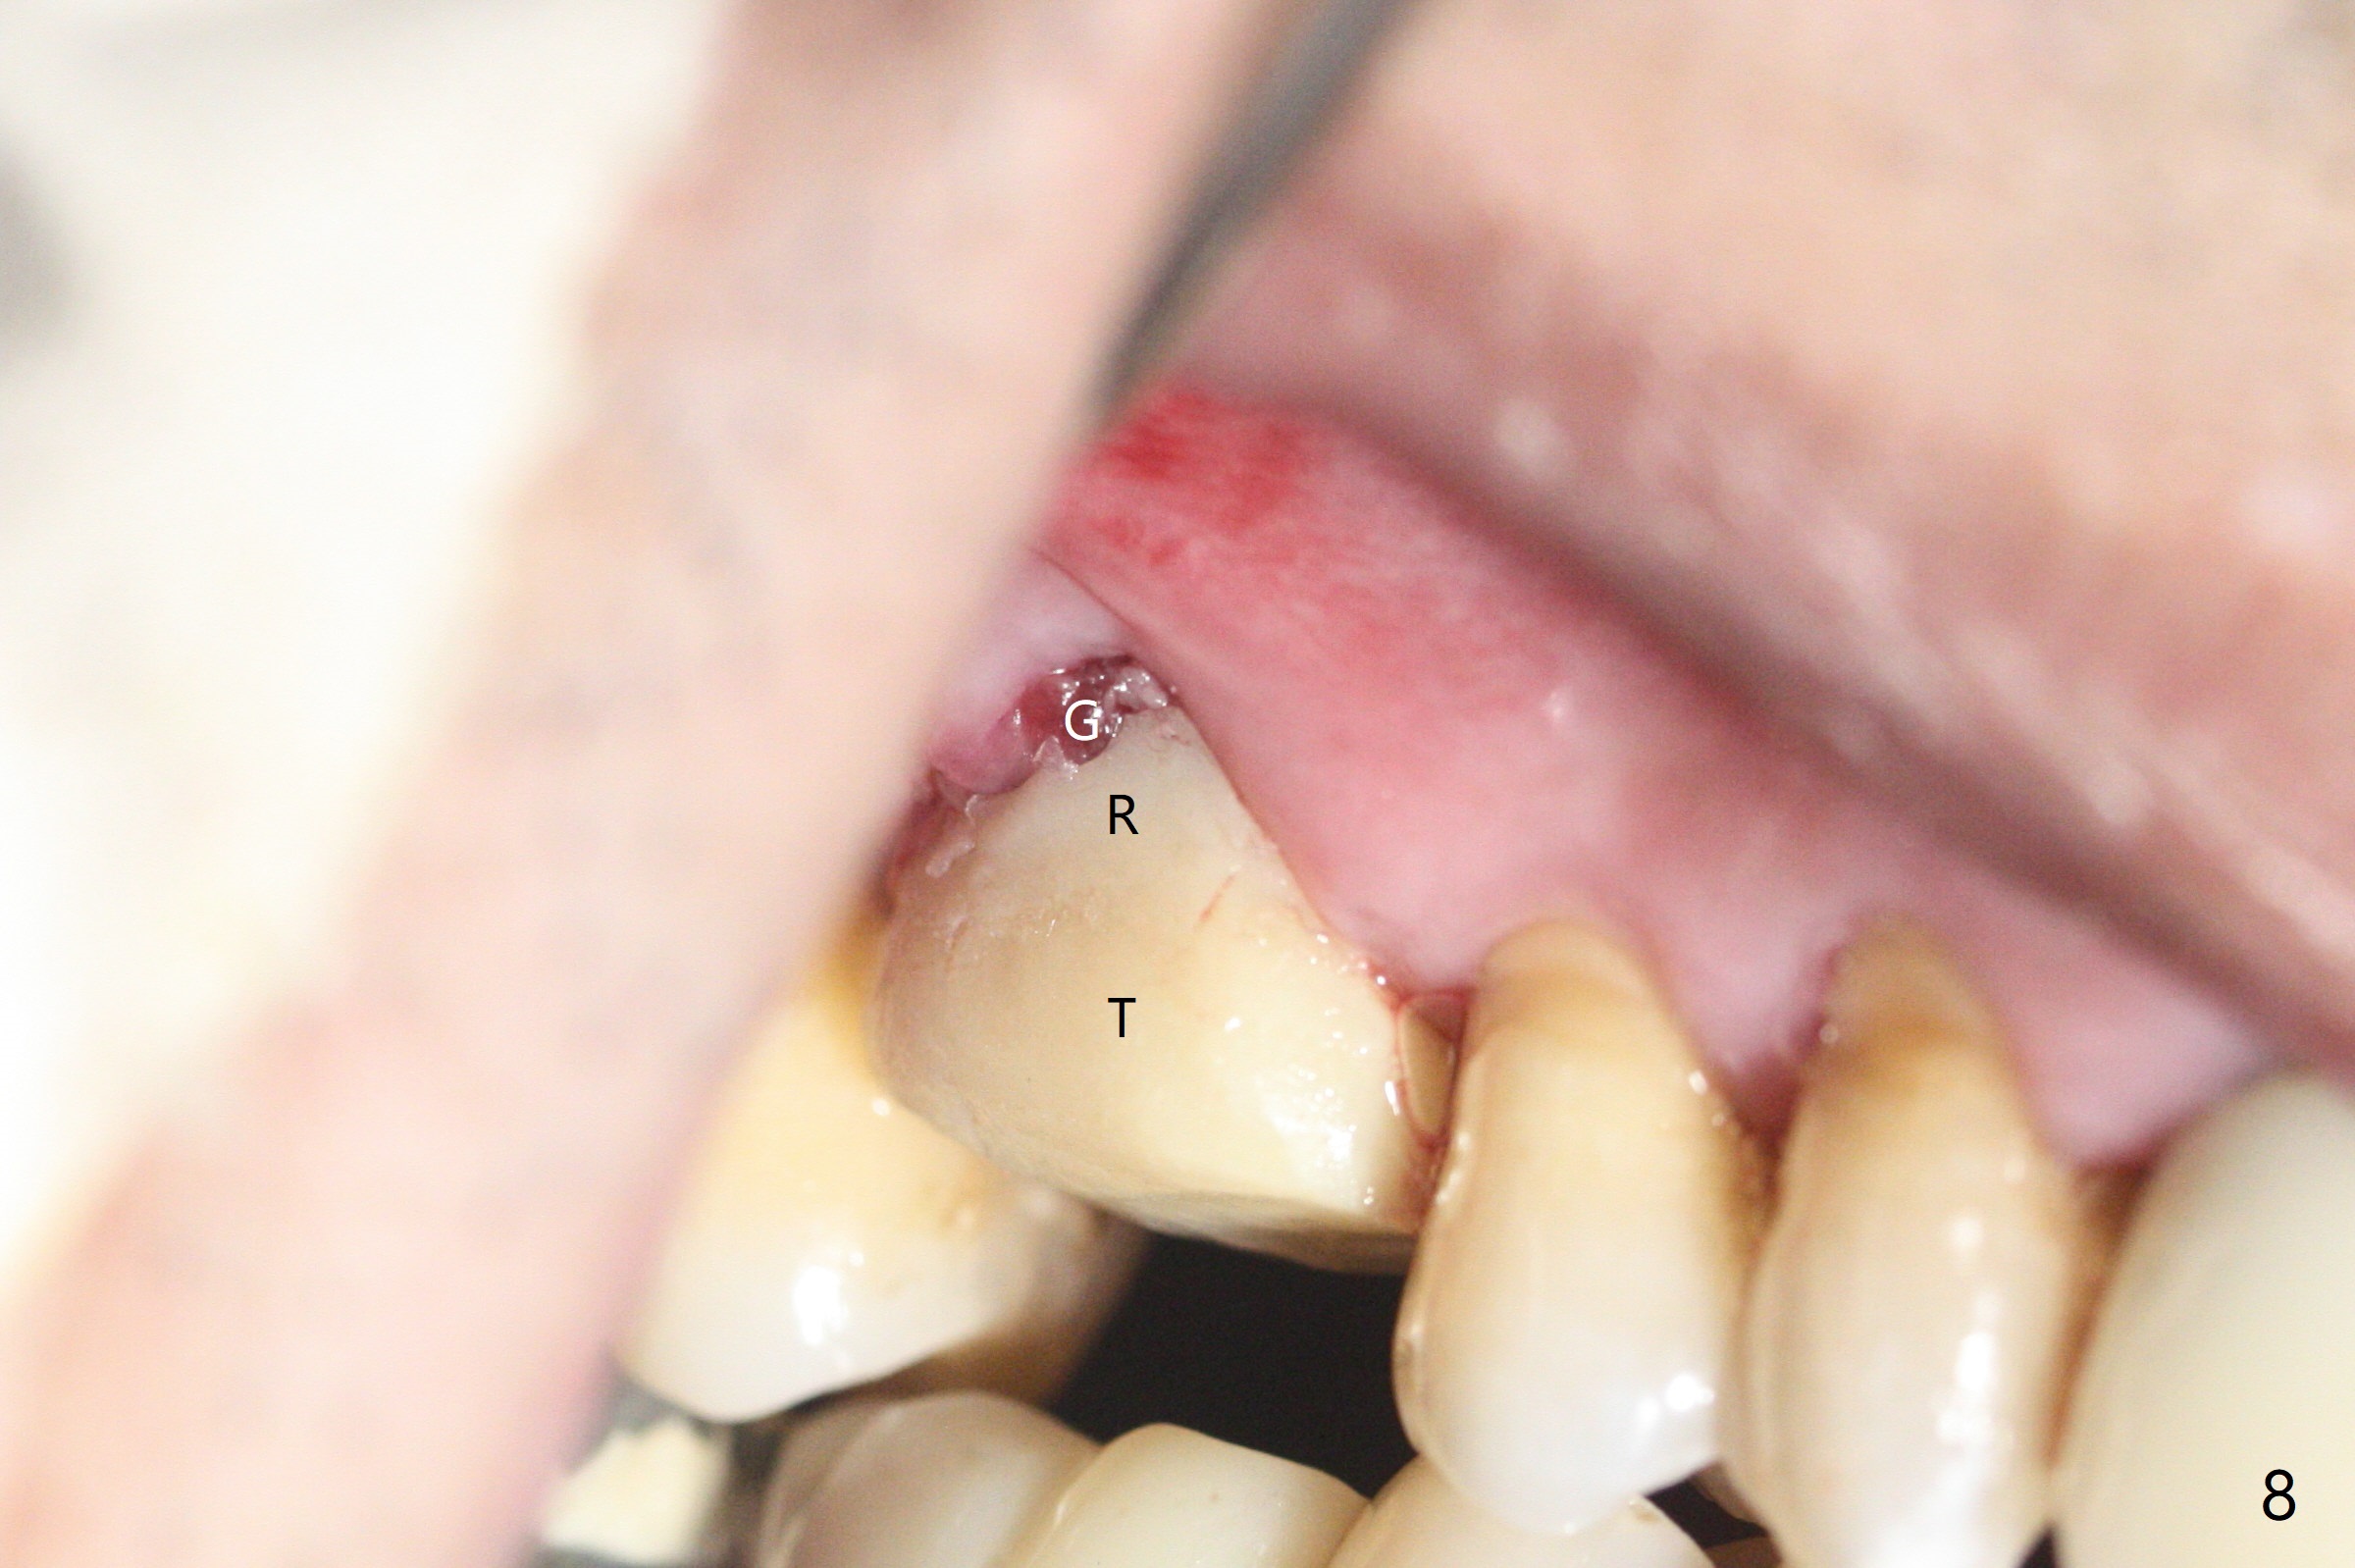

53岁男吸烟,牙周炎,咬合力大,3号牙颊侧(图一),腭侧(图二:P)牙龈退缩,尤其是近中颊侧根(图一:MB),拔牙后,中隔冠方(表面)有好像健康的牙龈(图三:*),近中,远中连接处切开(图三:虚线),将中隔牙龈推向近中颊侧牙槽窝(图四:箭头),修复退缩牙龈,而且暴露下面中隔(S),接着在它上面导板钻洞,避免软组织创伤。利用报废植体试图内提升(图五(红虚线:窦底)),最终正式植体完成提升(图六:黑*),初步在牙槽窝深部放置粘性骨粉(白*)后,放入基台,之后再次在植体,基台周围放置骨粉(图七:*),最后借助临时牙冠(图八,九:T)和外衬里(图八:R)封闭牙槽窝开口,G是近中颊侧迁移的牙龈。植体垂直进入上颌窦可以减少窦膜破裂(图五,六,九),术后没有鼻出血。术后1个月临时牙冠松动,去除牙冠和基台,安置愈合帽(图十)。表面骨粉遗失,但是颊侧移位的中隔牙龈好像帮助软组织预后。